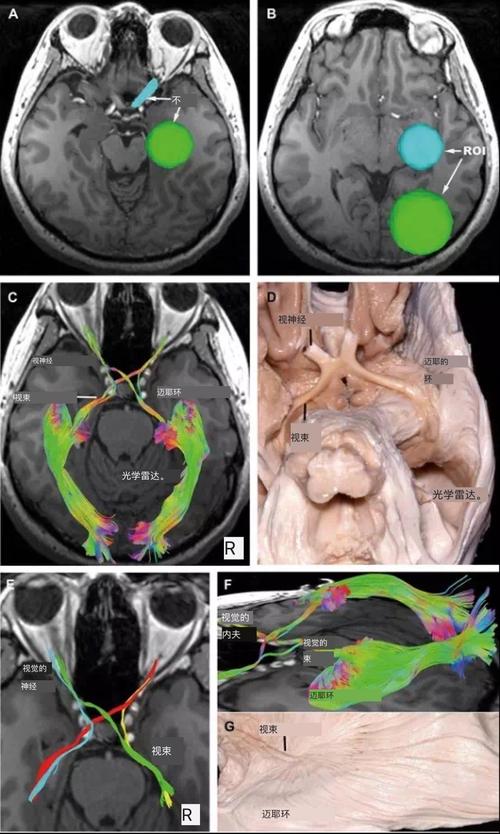

嗅神经解剖图,桡骨头解剖图

a,感兴趣区选在冠状位嗅神经束;b,高分辨率示踪嗅神经;c,对应的解剖